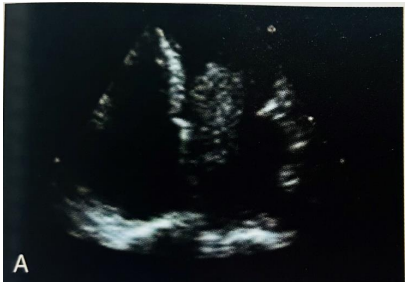

Paciente mulher, de 40 anos, sem comorbidades conhecidas,

chega à avaliação cardiológica com relato de tontura, tosse e

dispneia aos pequenos esforços iniciados há aproximadamente 1

mês.

Na consulta, traz imagem de ecocardiograma transtorácico, corte quatro câmaras, com descrição de massa em átrio esquerdo com densidade homogênea, contornos irregulares, móvel, com fixação em septo interatrial, projetando-se para cavidade do ventrículo esquerdo:

BRAUNWALD. Tratado de Doenças Cardiovasculares. 9ª Ed. Figura 74-1; página 1681.

Baseado no quadro clínico, na imagem apresentada e no diagnóstico mais provável, para as afirmativas a seguir, assinale (V) para a verdadeira e (F) para a falsa.

( ) É o tipo mais comum de tumor cardíaco primário. ( ) 90% dos casos está associado à ocorrência em pessoas da mesma família. ( ) A maioria dos pacientes se apresenta de forma assintomática. ( ) A maioria das lesões ocorre em mulheres.

As afirmativas são, respectivamente,